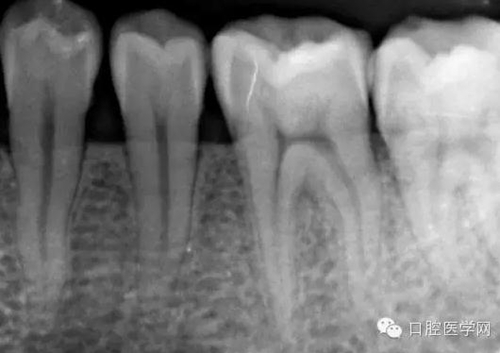

術(shù)中試尖x線片: